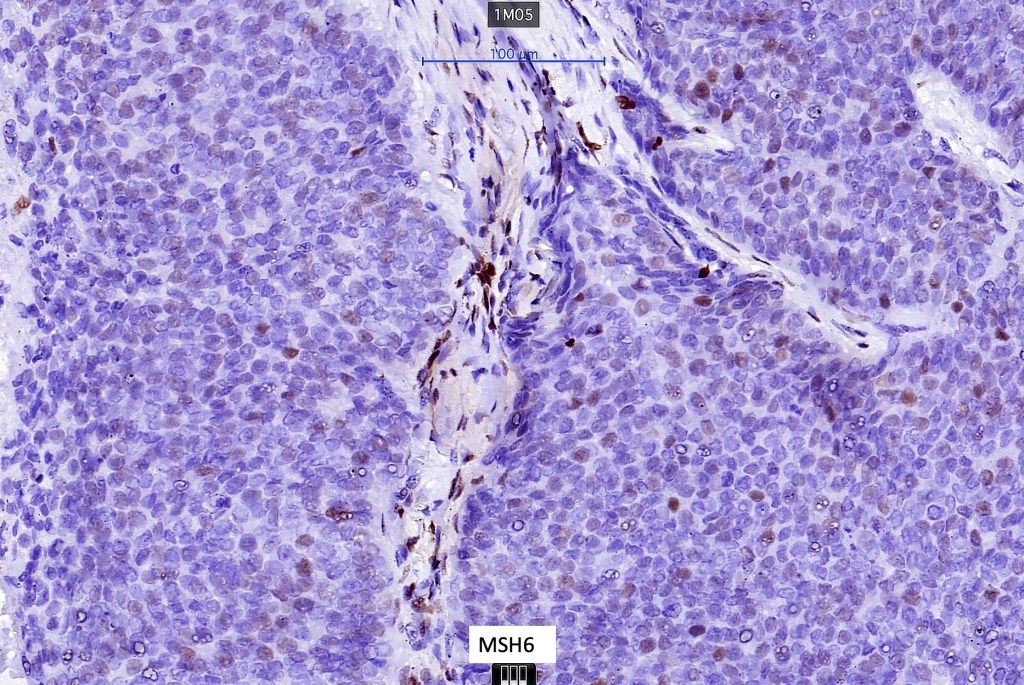

Sebaceous carcinoma from a patient with Muir-Torre syndrome kindly shared by Dr. Antonina Kalmykova.

Immunohistochemistry (from the Muir-Torre patient except for EMA which was shared by Dr. Tsheri Dorji